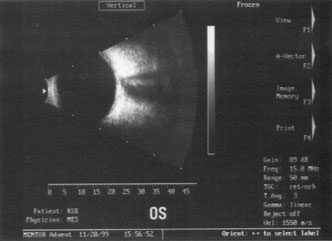

Back to Top